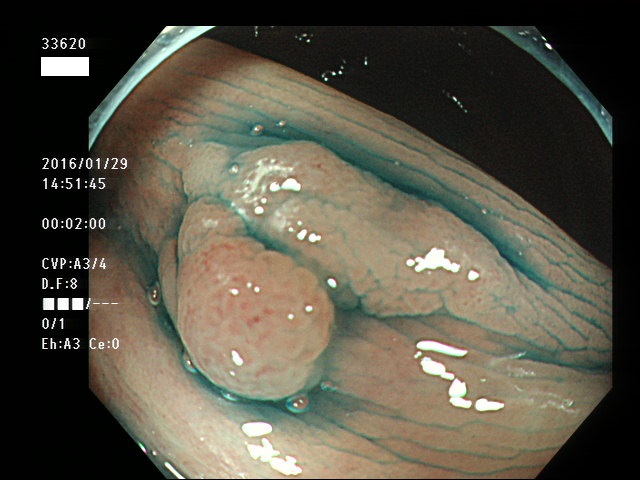

上記100名より抽出した平坦・陥凹型腺腫(=癌化の危険が高いが見落としやすい病変)の内視鏡写真